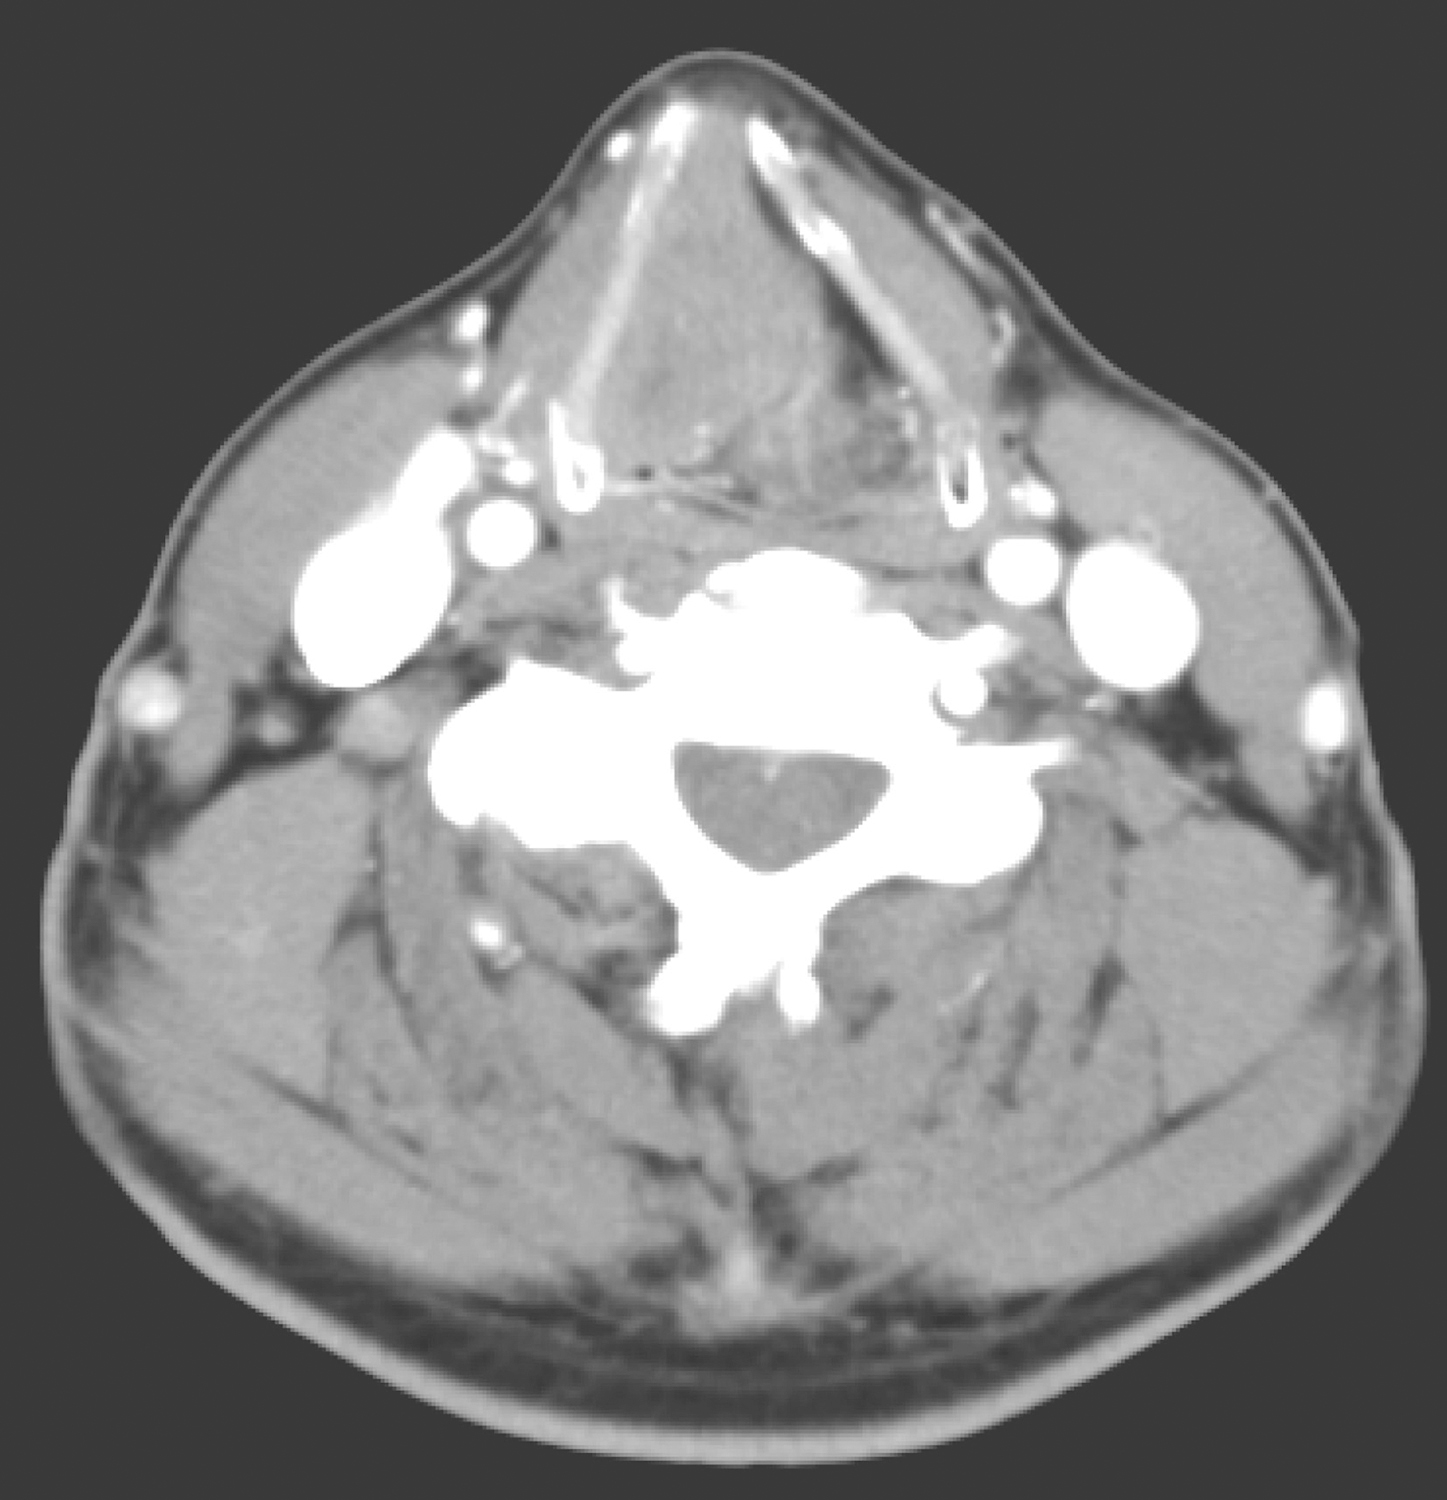

2.2017年3月15日颈胸部CT

检查所见:右侧室带、声带区肿物影,最大截面约1.8cm×3.5cm,病变侵犯右侧喉旁间隙,宽基底贴邻甲状软骨,凸向喉腔,推压对侧声带及室带,向前累及前联合(图2)。右颈部Ⅱ区类圆形肿大淋巴结,约1.0cm(图3),左颈部Ⅱ区、右侧气管食管沟淋巴结,大者短径约0.4cm。余纵隔散在小淋巴结。右肺中叶、下叶多发斑片、斑点状影,余肺未见明确结节及实变。

图2右侧室带、声带区肿物影、侵犯右侧喉旁间隙

引自:头颈部肿瘤多学科诊疗病例精选.第1版.ISBN:978-7-117-27929-1.主编:李正江

图3右颈部Ⅱ区类圆形肿大淋巴结

影像学诊断:

(1)右侧室带、声带肿物,符合癌。

(2)右侧颈部Ⅱ区转移淋巴结;左颈部Ⅱ区、右侧气管食管沟淋巴结,随诊观察。

(3)右肺中叶、下叶炎症。